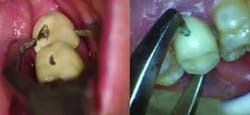

Fig. 1 — Dimple preparation on buccal surface of mandibular second molar PFM crown and palatal surface of maxillary second premolar PFM crown.